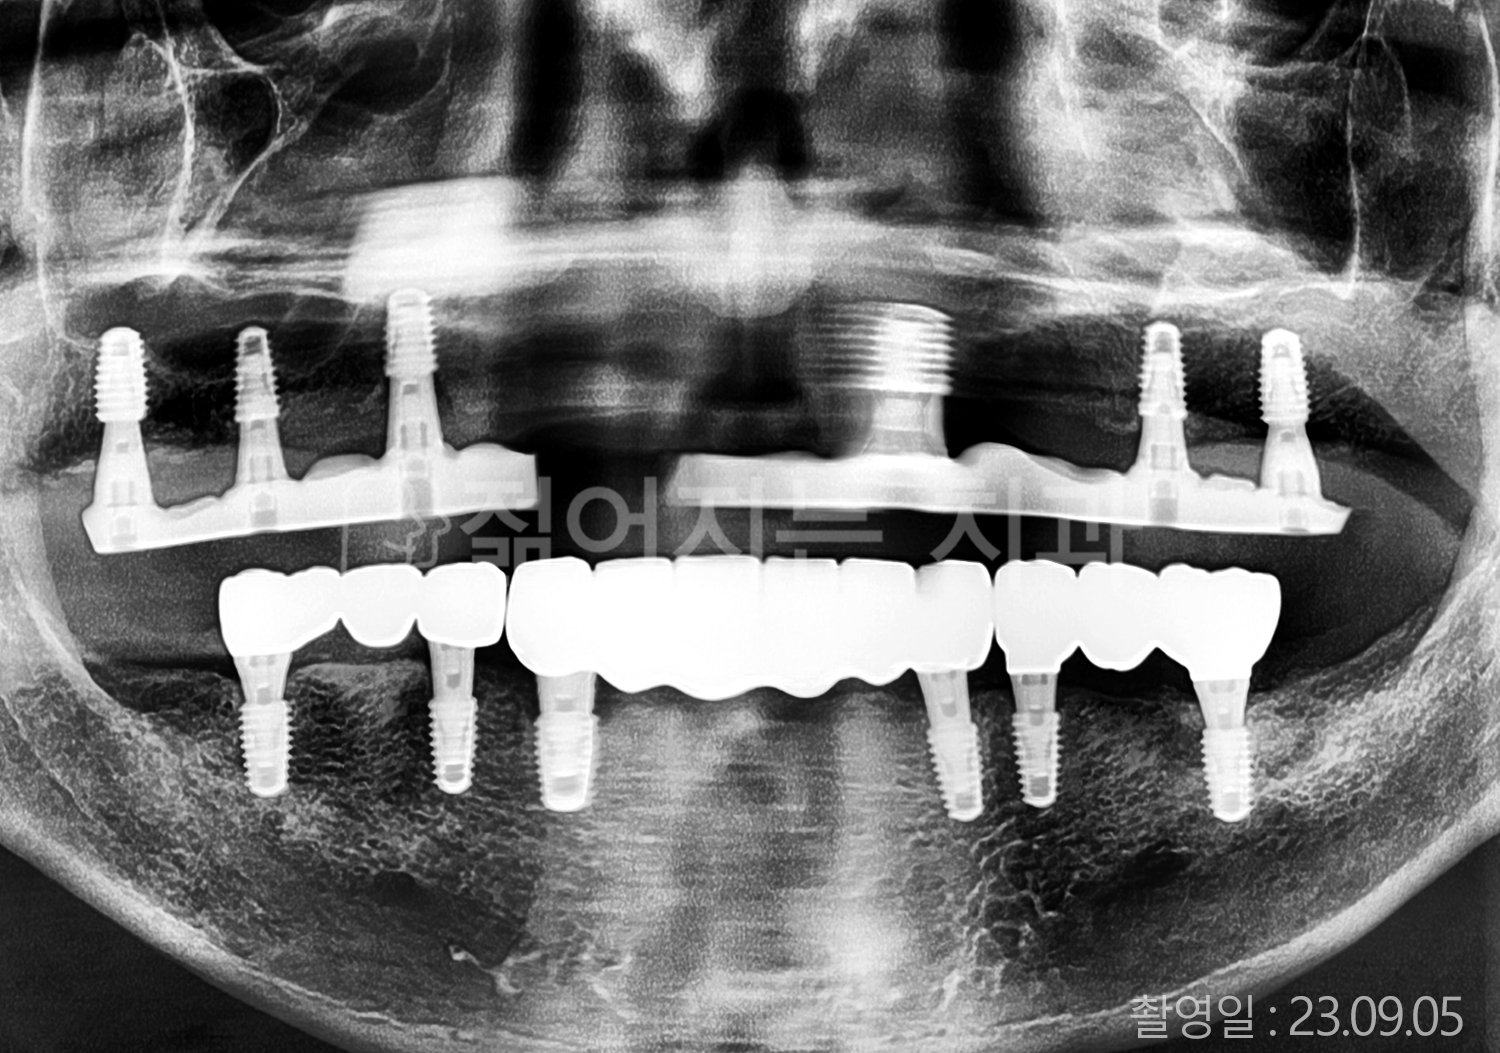

• 40대 전체치아 10개 이상 임플란트